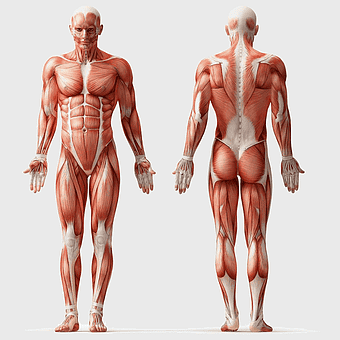

Breast cancer, musculoskeletal system, human anatomy, health care, skeletal muscle structure, medical illustration, body composition analysis -

human anatomy diagram, muscular system illustration, human body muscles, fitness anatomy chart, skeletal muscle structure, human physiology study, muscle group analysis